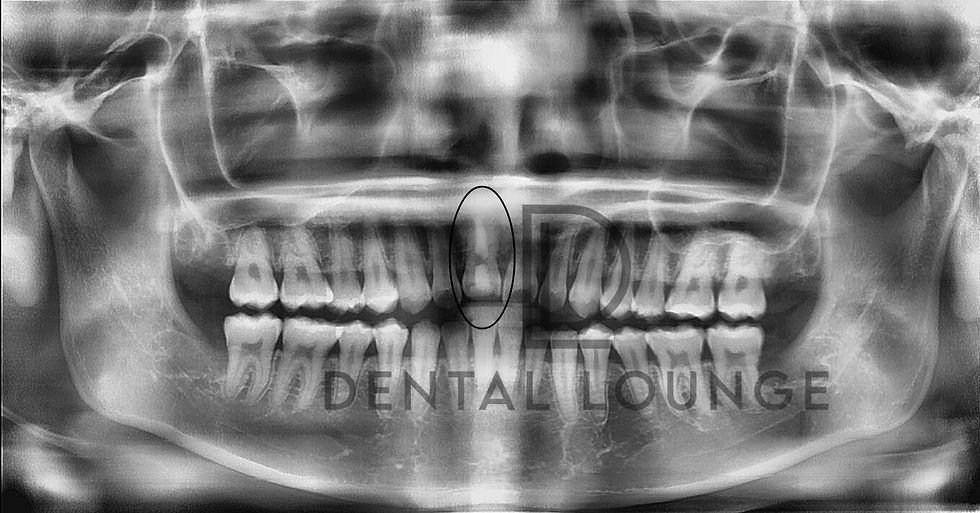

Surgical Removal of Buried and Impacted #38 Under Local Anesthesia

Patient presented with pain associated with a buried and vertically impacted lower wisdom tooth (#38). Following CBCT evaluation and nerve assessment, surgical removal was completed under local anesthesia using bone guttering and tooth sectioning techniques for safe removal.